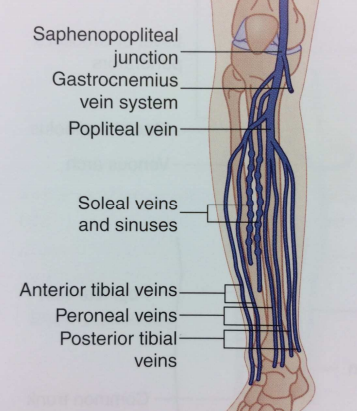

Veine tibiale antérieure

Tronc tibioperonier

Veine péronière (fibulaire)

Veine tibiale postérieure

Veine petite saphène (TVS)

Veines Jambières

Schema

Veines jumelles (gastrocnemiennes)